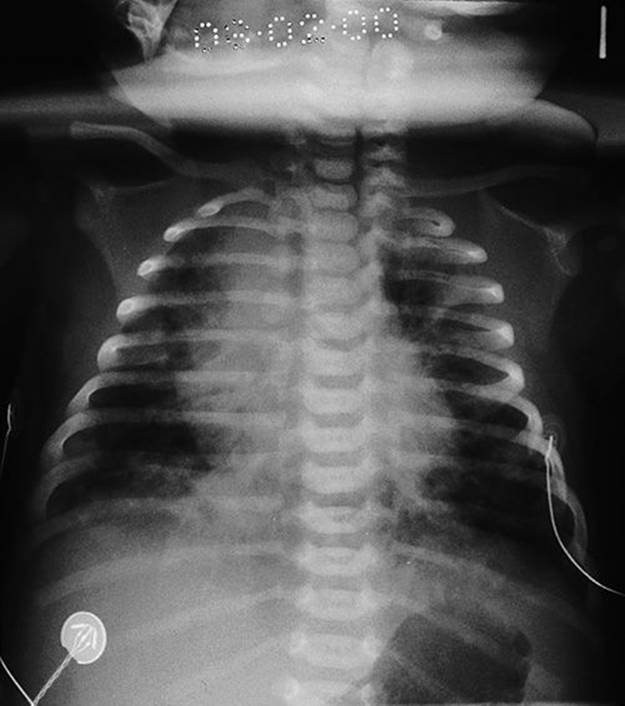

Meconium aspiration syndrome is also a potentially serious respiratory complication. In utero, meconium is usually retained within the colon. Although it may be passed through the sphincter under physiological conditions, particularly after 40 weeks, it also has an association with fetal hypoxic stress. Meconium is irritative to the neonatal lungs and may lead to a pneumonitis, the meconium aspiration syndrome (Fig. 50.2). Clinical features range from mild neonatal tachypnoea to severe respiratory compromise. The incidence is probably unrelated to fetal pH (and indeed the majority of babies with meconium aspiration syndrome are not acidotic at delivery) but the syndrome is more likely to be severe if there is associated acidosis. It is also more severe when the meconium is thick. Treatment is with oxygen, mechanical ventilation, surfactant therapy (as meconium can displace or inactivate endogenous surfactant) and, if very severe, extracorporeal membrane oxygenation ± pulmonary lavage.

FIG. 50.2Meconium aspiration syndrome.

Note the widespread patchy shadowing in both lungs.